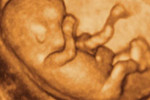

Badanie USG dostarcza przyszłym rodzicom ogromnych wrażeń. Można przecież po raz pierwszy zobaczyć swoje dziecko. Jednak najważniejsze jest to, że można upewnić się, że u maluszka wszystko w porządku.